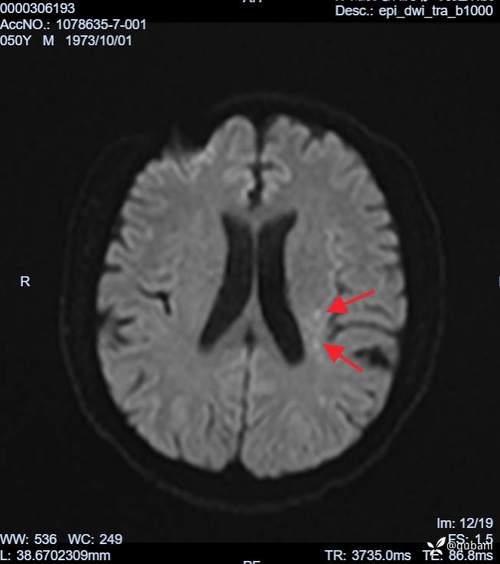

术中血栓形成与脱落:

(图片来源网络,侵删)- 人工瓣膜和人工血管:手术中植入的人工瓣膜和人工血管表面不是我们自己的组织,血液流过时容易形成血栓,术中如果血栓形成,或在操作中脱落,就可能随血液循环进入脑动脉,造成堵塞。

- 长时间体外循环:Bentall手术需要在体外循环(心肺机)支持下进行,血液在体外循环中与管道、氧合器等非人体表面接触,容易激活凝血系统,形成微小血栓,这些栓子也可能进入大脑。

在心脏和大血管的操作中,如果不慎将空气注入血管,空气栓子会随血流到达脑血管,引起脑梗,这是心脏外科手术需要极力避免的严重并发症。

- 手术需要钳夹、切开、缝合主动脉,这个过程可能导致主动脉壁上的动脉粥样硬化斑块脱落,脱落的斑块是一个大栓子,极易堵塞脑血管,造成大面积脑梗。